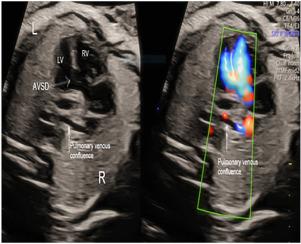

胎儿诊断心上全肺静脉连接异常的三血管透视线索

Clues on the Three-Vessel View for Fetal Diagnosis of Supracardiac Total Anomalous Pulmonary Venous Connection